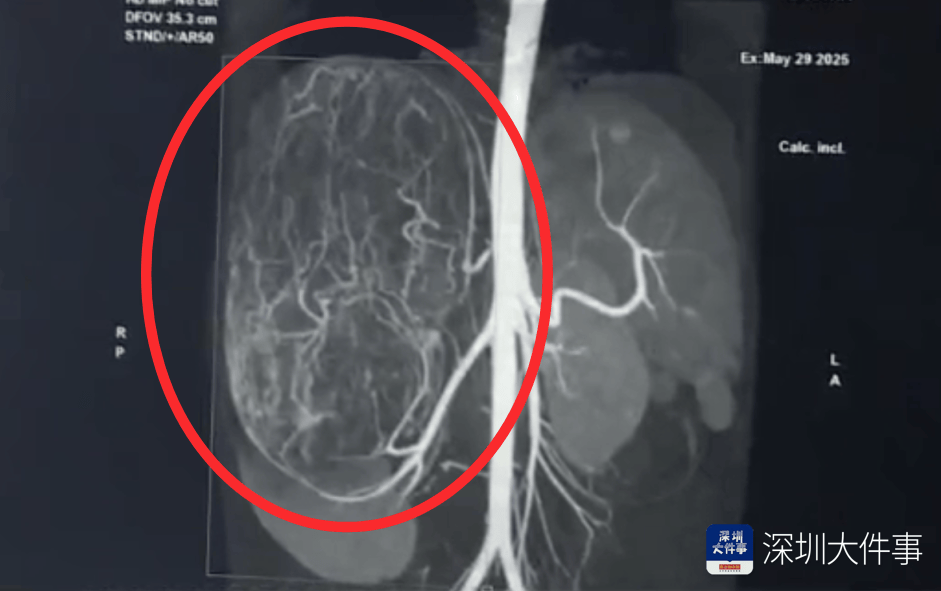

17岁的汕头女孩婷婷(化名) 平时活蹦乱跳 能吃能睡 身材非常苗条 谁承想 一次平平无奇的逛街买衣服 店员一句善意的提醒 竟让她发现肚子里 有一个大如篮球的肿瘤...